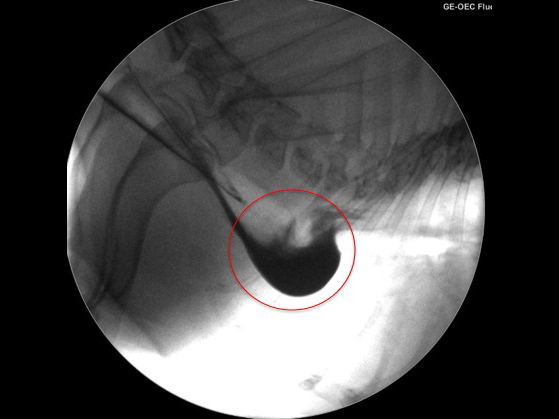

ご飯を食べるとすぐに吐いてしまうとのことで来院されました。

問診をして食道の動きの問題であることが疑われたのでバリウムという造影剤を飲ませてCアームで撮影してみると・・・

上のような画像が得られました。

赤丸で囲われているところに黒い造影剤が溜まっているのが分かります。

この所見は巨大食道症という病気でみられます。

この症例は巨大食道症により食道が拡張し、赤丸のところに食べたもの・飲んだものが溜まって吐いてしまっていたのです。